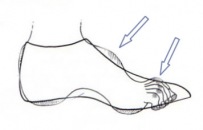

Többnyire a betegesen túlívelt lábboltozat (pes excavatus, pes cavus) esetében van az, hogy a cipő konfliktusban van a lábbal a láb hátoldalán: nyomja a lábat a cipő fűzője és a cipő más záró elemei.

Többnyire a betegesen túlívelt lábboltozat (pes excavatus, pes cavus) esetében van az, hogy a cipő konfliktusban van a lábbal a láb hátoldalán: nyomja a lábat a cipő fűzője és a cipő más záró elemei.

Olyan cipővel lehet e fájdalmas problémát megoldani, melynek a nyelve szivaccsal van jól kibélelve és a cipő nem fűzős, hanem tépőzáras.

A magasan ívelt lábboltozat miatt konfekció cipő nehezen található az ilyen lábra.